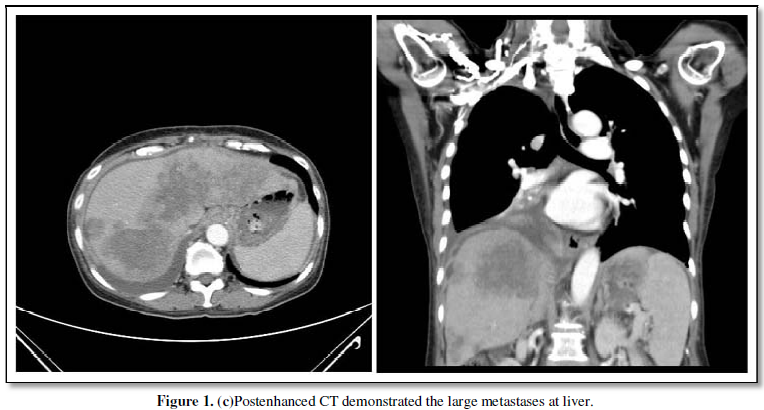

calcified lymph nodes at the bilateral hilar regions (Figure 1b). Postenhanced

CT demonstrated large metastases at the liver (Figure 1c). Although

accumulation of Tc-99m MDP in liver metastases with no apparent calcification

occurs frequently in colon cancer, no characteristic Tc-99m MDP uptake was observed

within those metastatic lesions.